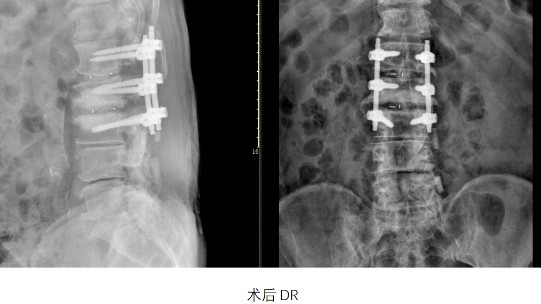

滬甬兩地脊柱團隊精準操作,經過3個半小時的高強度手術,手術團隊相繼完成腰1-2、2-3椎板切除椎管擴大減壓、椎間橫突間植骨融合、脊柱滑脫復位椎弓根釘內固定、脊髓和神經根粘連松解、腰椎翻修內固定取除術等多項手術,最終都獲得成功。

術后3天,童老爺子在佩戴支具后已經可以自如行走,家屬和醫護人員們都感到高興。童老爺子自己也說:“重新翻修完后,感覺自己又回到了年輕時候,非常感謝華山醫院和九院的專家們?!边@場跨越兩代醫者的生命接力,不僅續寫了患者的安康,更銘刻著時代浪潮中不變的醫者初心。